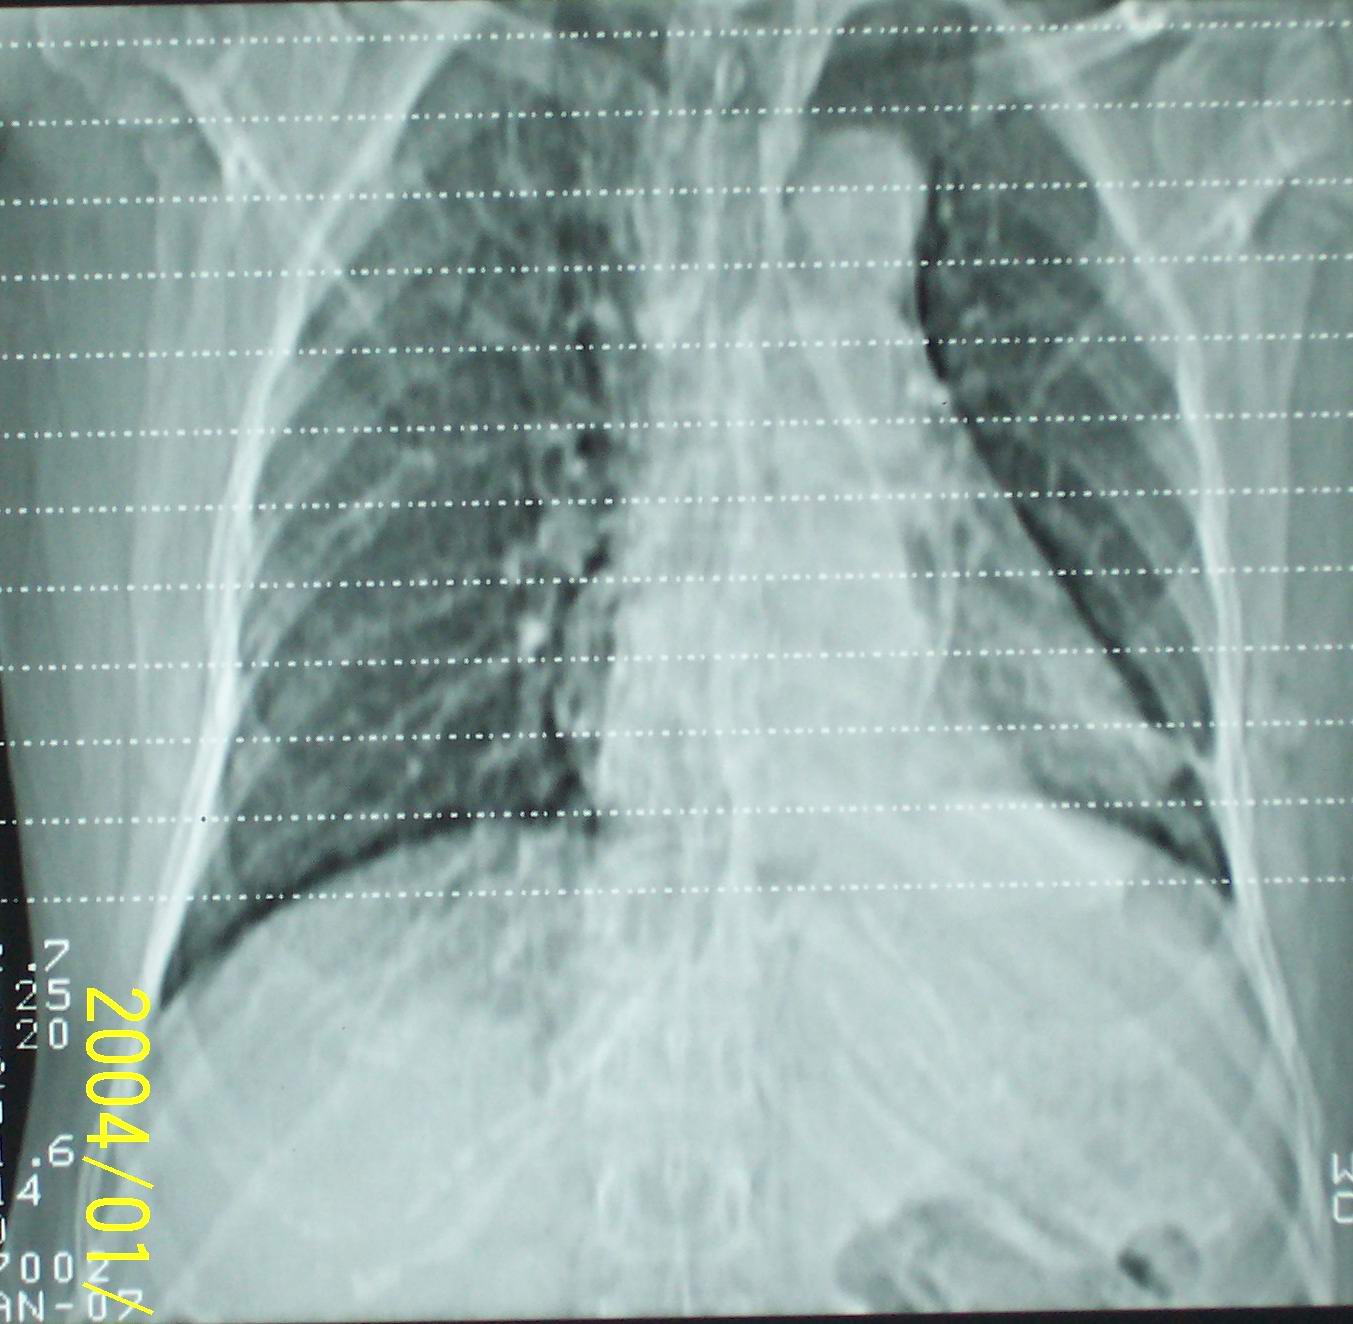

53岁女性,间断性腰部困疼、乏力一年,活动时加重。

左肺下叶后基底段片状实变影,密度均匀,左肺体积缩小,膈肌上提.考虑:左下肺肺不张.

1.左侧胸腔无明显萎陷,肺体积缩小,含气量减少,纵隔心脏左移。从这个意义来讲,左下肺病灶应该首先考虑肺不张。

2.左下肺病灶密度太过均匀,边缘过于光整锐利,位置特殊,其次应该考虑隔离肺的可能。

3.连续观察不能完全否定病灶是疝入胸腔的脾脏(扫描不怎么规范,跨越过大),所以膈疝也需要考虑。

补充一下病史:三天前因咳嗽咳血检查胸片见左下肺索条状影,后复查ct